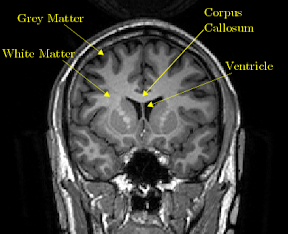

二、灰質(Grey matter):灰質由神經元(Neuron)、神經膠質細胞(Neuroglial Cell)及微血管(Capillary)組成。而灰質的灰色源於神經元的細胞體(cell body, or soma)和微血管。

灰質是中樞神經系統(Central nervous system)(註十)中神經元(Neuron)大量聚集的部位。主要分佈於大腦皮質(Cerebral cortex)(註十一)、小腦皮質(Cerebellar cortex)(註十二)、小腦深部核團(Deep cerebellar nuclei)(註十三)、丘腦(Thalamus)(註十四)、下視丘(Hypothalamus)(註十五)、基底核(Basal ganglia)(註十六)、腦幹(黑質,紅核,橄欖核、腦神經的核團等),以及脊髓的深部(即脊髓灰質)。

典型的灰質(Grey matter),例如大腦皮質(Cerebral cortex)中,神經元(neuron)之間存在著大量化學突觸(chemical synapse)或電突觸(Electrical synapse)作為通信管道,形成極其複雜的神經迴路(never circuit),可讓多種多樣的感覺(sensory neuron)、運動(motor neuron)或中間(interneuron)信息在此迴路中處理。所以灰質(Grey matter)是中樞神經系統(Central nervous system)對信息進行深入處理的部位。相較之下,白質由神經元的軸突(Axon)組成,所以本身不具有處理信息的功能,僅僅在不同灰質之間或者灰質與周圍神經系統(Peripheral Nervous System)控制的器官之間傳遞信息。

大白話就是灰質(Grey matter)是CPU或者記憶體(Computer memory;RAM)中的那些一個個顆粒啦!白質(White matter)就是主機版中的積體電路(integrated circuit)。